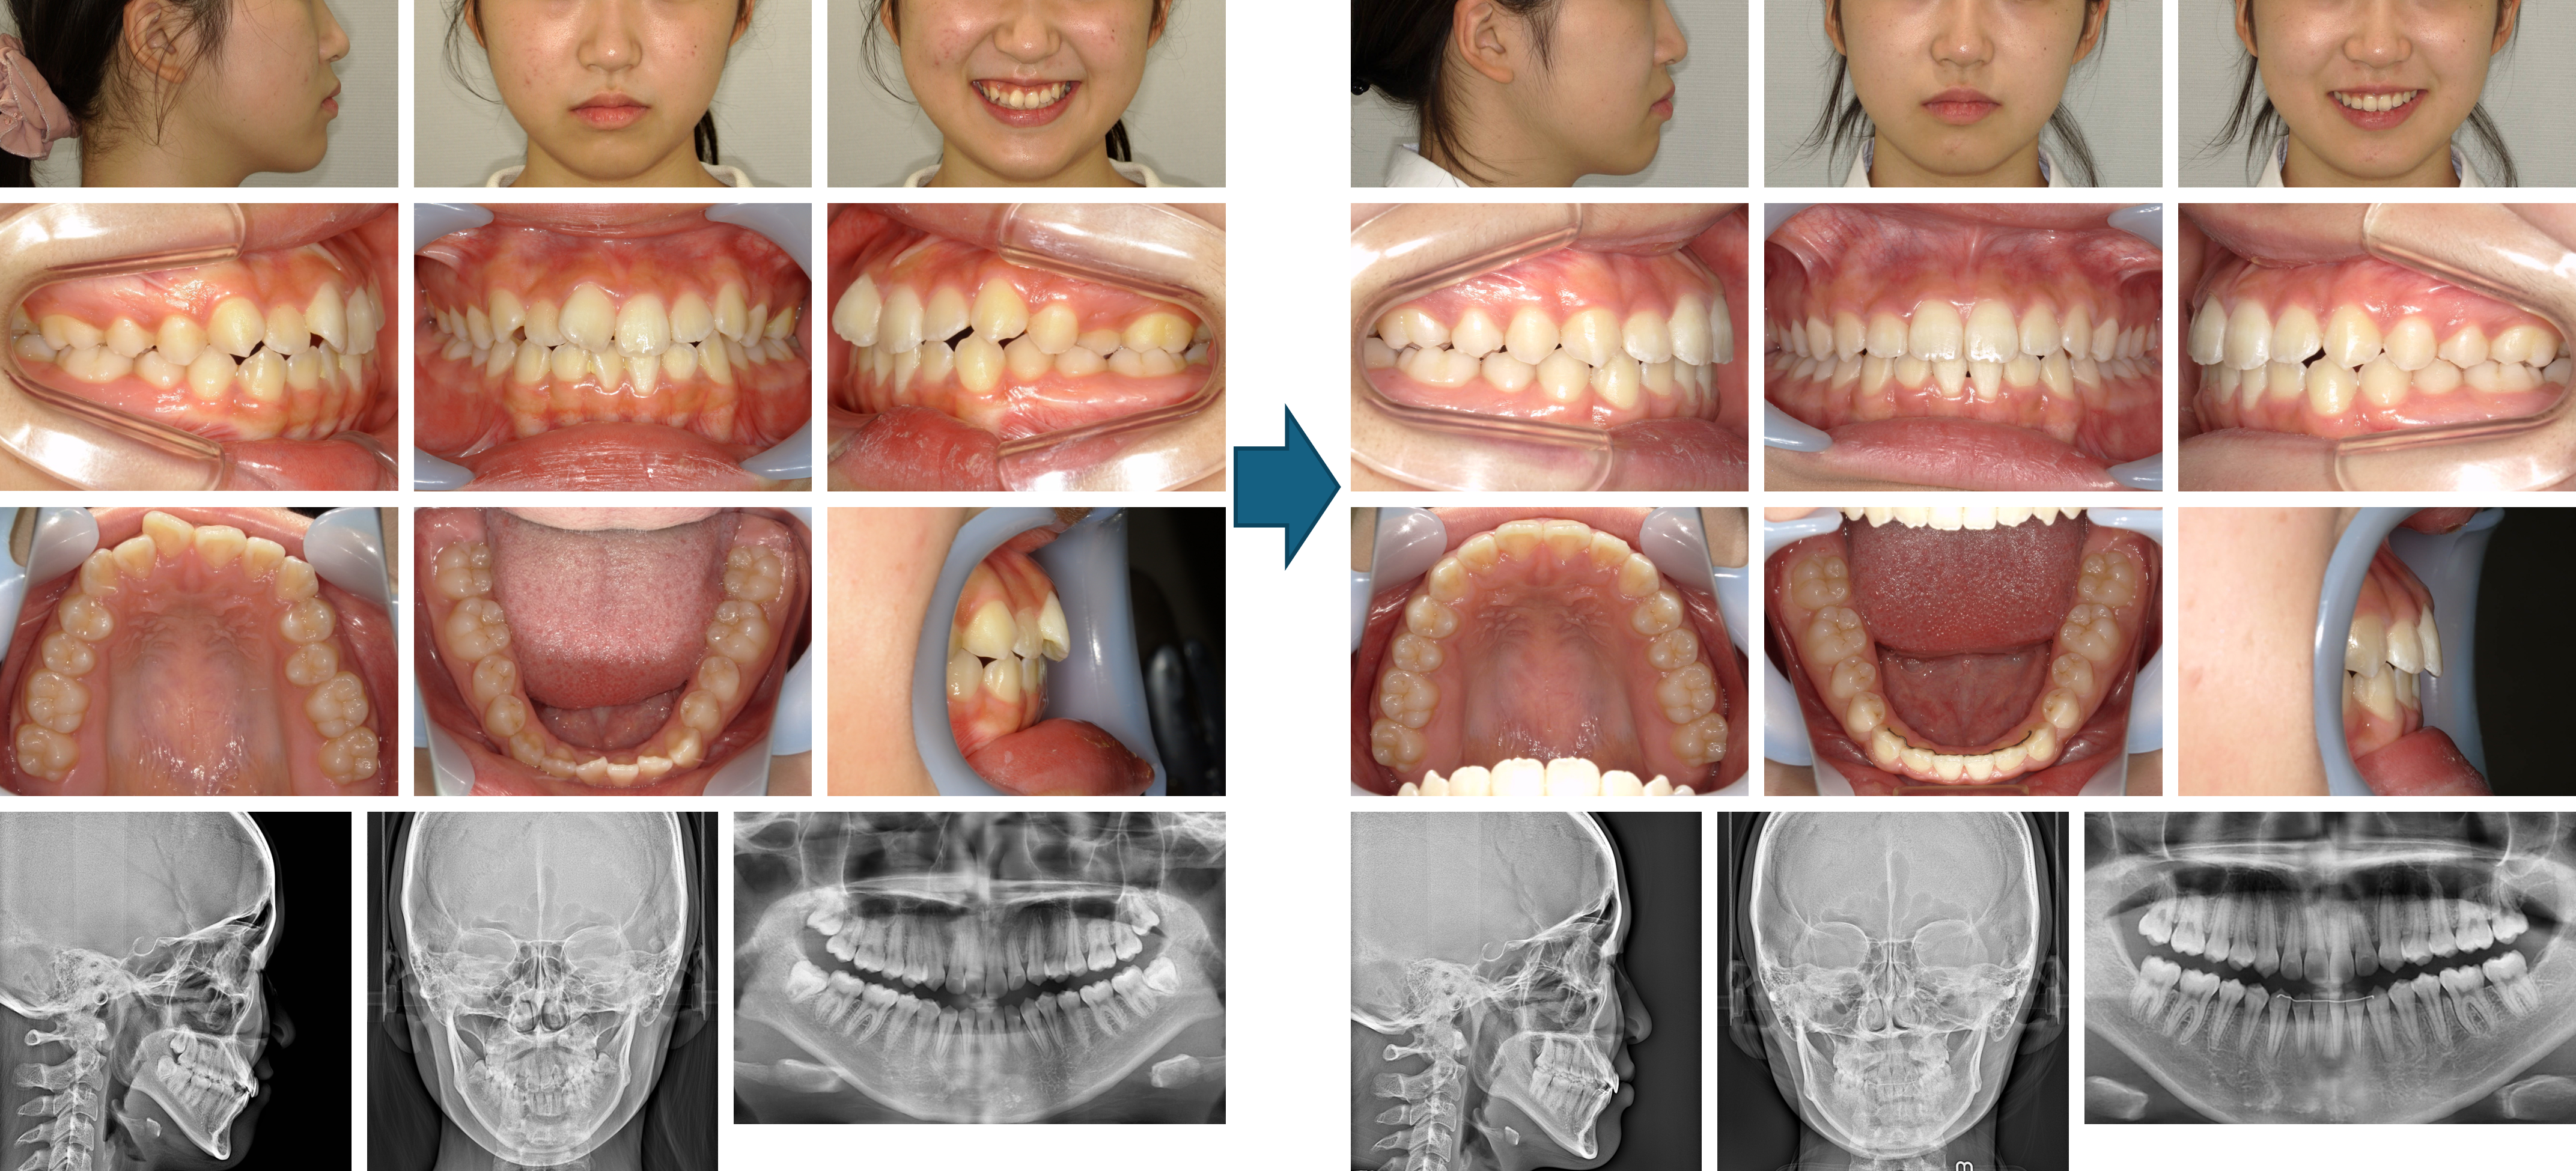

【治療例】初診時年齢:22歳3か月 / 性別:女性 / 主訴:ガタガタ

治療の概要:上下歯列の叢生および正中線のずれを主訴に来院した。

治療開始前に埋伏していた親知らず4本を抜去後、マウスピース型(アライナー型)矯正装置(インビザライン®)により臼歯の遠心移動と歯間隣接面削合(IPR)を行った結果、緊密な咬合を獲得することが出来た。

主訴:ガタガタ

診断名:叢生

使用した主な装置:マウスピース型(アライナー型)矯正装置(インビザライン®)、IPR、顎間ゴム

抜歯/非抜歯および抜歯部位:非抜歯

※こちらの症例は2019年3月から2021年1月に行った矯正治療です(現在も経過観察中)

治療期間:1年10か月

治療回数:22回